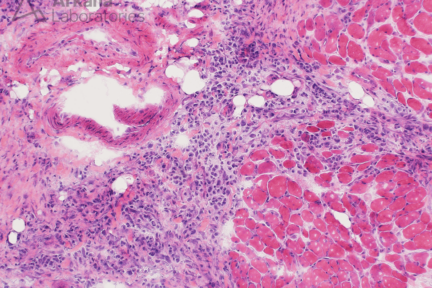

Signet Ring Carcinoma

Clinical History This 50-year-old patient presented with muscle weakness and stiffness. They had recently been identified to have diffuse thickening…